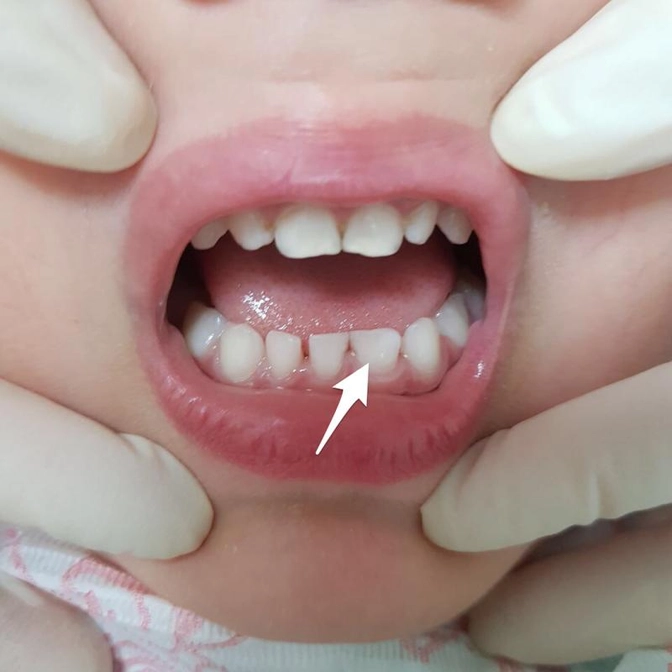

Вижу то, что на фото.

Смотрите какой большой зуб указан стрелкой.

Он явно шире «соседей».

А количество зубов от клыка до клыка считали?

Должно быть 4, а их 3.

Закладка молочных зубов происходит в первый триместр беременности.

В этот период, судя по всему, произошел сбой.

И это поспособствовало «слиянию» двух будущих зубов в один, но побольше.

Это вовсе не означает, что с постоянными зубами ситуация повторится.

Узнать это наверняка можно двумя способами:

1. Дождаться смены (примерно 6-7 лет)

2. Сделать прицельный снимок данного участка.

И тут все зависит от ребёнка (насколько он не против) и от его родителей (насколько им важно это знать сию минуту)

Поскольку в данном случае снимок НИЧЕГО, кроме как утоления любопытства, не даст.